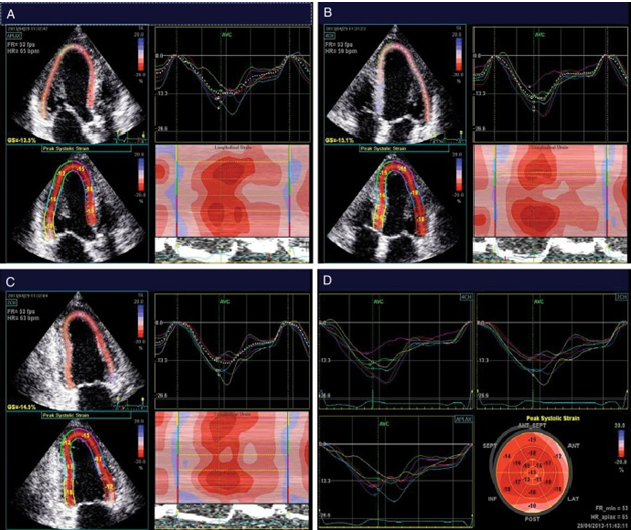

Технологии не стоят на месте, и несколько лет назад появилась новая технология, , такая как оценка деформации ЛЖ по данным спекл-трекинг (Speckle tracking) эхокардиографии (СТЭ или CLS) не связанная с доплеровским исследованием, а основанная на оценке движения миокарда по стандартной серой шкале, по стандартному серошкальному изображению.Технология получила название Speckle tracking на английском языке или на русском языке – это технология оценки деформации по двухмерному изображению. И, не вдаваясь в детали, можно сказать, что, анализируя стандартные эхокардиографические позиции: четырехкамерную, трехкамерную и двухкамерную позицию – довольно быстро, в течение 2-3 минут, можно получить интегральную оценку сократимости левого желудочка, условно можно назвать так, или деформацию левого желудочка, получить аналог фракции выброса (ФВ). В чем преимущество этого показателя? В первую очередь в очень высокой воспроизводимости. Глобальная продольная деформация левого желудочка – значительно более устойчивый показатель, чем фракция выброса левого желудочка. И уже разработано нормативное значение глобальной продольной деформации. В норме оно составляет около 18%. Технология новая, поэтому, конечно, существуют определенные проблемы. Каждый ведущий производитель диагностического оборудования реализует эти технологии немного по-разному. И поэтому значения на одном приборе могут не совпадать со значениями на другом приборе. Поэтому рекомендуется при мониторинге пациентов использовать все-таки один и тот же прибор.

Было доказано, что снижение глобальной продольной деформации наступает значительно раньше, чем снижение фракции выброса левого желудочка. Уже спустя несколько месяцев после начала химиотерапевтического лечения мы видим, что у значительной части пациентов, практически у половины, происходит снижение более 1-%. Это уже клинически значимое снижение глобальной продольной деформации, при этом фракция выброса фактически не снижается. И только спустя уже какое-то продолжительное время мы начинаем видеть уже снижение фракции выброса левого желудочка. Очень важно было показано, что снижение вот этой глобальной продольной деформации в ранние сроки позволяет с достаточно высокой чувствительностью и специфичностью предсказать дальнейшее снижение фракции выброса левого желудочка.

Нормальные значения для показателя глобальной продольной деформации ЛЖ составили –18,9±2,5%

Технология «спекл трекинг» (speckletracking)и ее разновидность — глобальный пиковый систолический стрейн (CLPS LV%). существенно расширила возможности диагностики. Если классическая эхокардиография позволяет диагностировать изменения структуры и функции миокарда, то с помощью этого метода можно точно оценивать механику миокарда и выявлять в нём самые ранние, скрытые изменения.